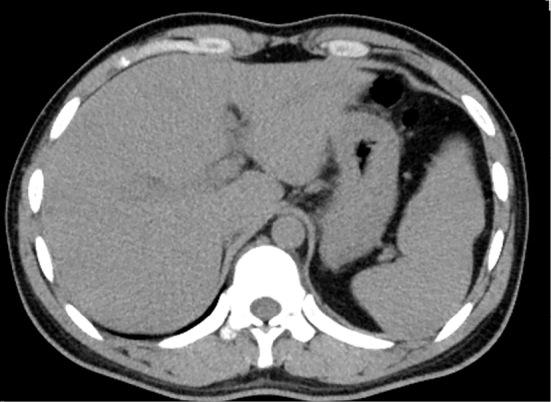

A 26-year-old Indian man who had arrived in Japan 24 days prior presented to our hospital with abdominal pain and a fever. A blood test revealed marked hepatic dysfunction, and imaging tests confirmed a diagnosis of acute hepatitis. The patient's liver function and coagulability deteriorated, and his general condition was poor. Given the possibility of fulminant hepatic failure, we initiated steroid pulse therapy. Following the initiation of steroid therapy, the patient's liver function and subjective symptoms rapidly improved. Testing revealed positive findings for IgA-hepatitis E virus, and a genetic analysis of hepatitis E identified genotype 1, which is not endemic to Japan, leading to a definitive diagnosis of imported hepatitis E infection from India. The successful response to steroid therapy highlights the potential benefit of this approach in managing severe cases of acute hepatitis E, a rare occurrence in Japan. This case underscores the importance of considering hepatitis E infection in individuals with a recent travel history to regions with high prevalence and the potential benefits of steroid therapy in managing severe cases of acute hepatitis E.

一位 26 岁的印度男性,24 天前抵达日本后出现腹痛和发热,到我院就诊。血液检查显示明显的肝功能障碍,影像学检查确诊为急性肝炎。患者的肝功能和凝血功能恶化,一般情况较差。鉴于可能发生暴发性肝衰竭,我们开始使用类固醇脉冲疗法。类固醇治疗开始后,患者的肝功能和主观症状迅速改善。检测发现 IgA 型戊型肝炎病毒阳性,戊型肝炎的基因分析确定为基因型 1,这种基因型在日本并非地方性流行,因此明确诊断为从印度输入的戊型肝炎感染。类固醇治疗的成功反应表明,这种方法在治疗日本罕见的严重急性戊型肝炎病例中可能具有益处。本病例强调了在有近期旅行史前往戊型肝炎高发地区的个体中考虑戊型肝炎感染的重要性,以及类固醇治疗在管理严重急性戊型肝炎病例中的潜在益处。